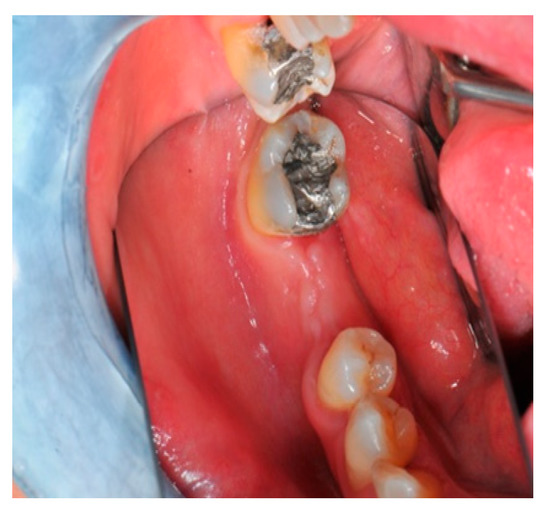

- Flap design: Soft tissue management should be as accurate as possible. The design of the flap should ensure a tension-free primary closure of the wound even after voluminous grafting of the defect. One option (preferred especially in wide vertical defects) is the execution of the so-called “poncho” flap. This technique includes a high vestibular incision of the mucosa, muscle and periosteum in order to undermine the preparation of the flap and to achieve its mobilization, followed by a deep incision in the buccal area with two additional vertical incisions that are performed at an appropriate distance from the occlusal area and the site of augmentation. After the incision, the preparation of a muco-periosteal flap and the remotion of scar tissue, a full thickness flap is raised until the bone defect is uncovered [17,18,19,20]. Finally, the positioning of the customized titanium mesh is passively tested to evaluate its fit intra-operatively (Figure 2, Figure 3, Figure 4 and Figure 5).